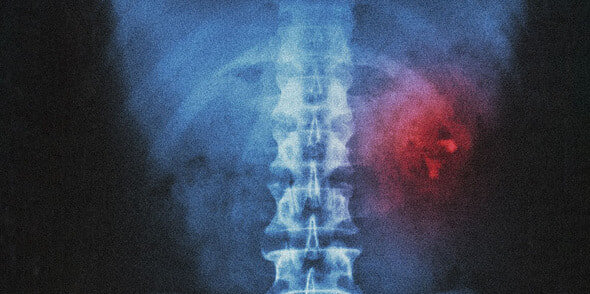

Чтобы понять, как именно болят почки, сначала обозначим, где они находятся. Почки — парный орган, расположенный в забрюшинном пространстве в районе поясницы. Они размером с кулак и по форме напоминают фасолины. В день почки фильтруют примерно 2000 литров крови и выводят с мочой шлаки, отходы и лишнюю воду. Кроме того, они регулируют водно-солевой обмен, нормализуют давление, производят гормоны и выполняют другие важные для организма функции.

Боли в пояснице и не только

Острая боль локализуется в поясничной области, справа или слева от позвоночника. При этом она может иррадиировать, или, проще говоря, отдавать в другие зоны по ходу мочеточника — вниз живота, во внутреннюю поверхность бедра, а иногда и в наружные половые органы. Симптомы почечной колики путают с неврологическими болями, и это плохо. Главный признак, что болят именно почки, — общее недомогание. Боль сопровождают слабость, усталость, головные боли, при этом компрессы и мази для спины не помогают.